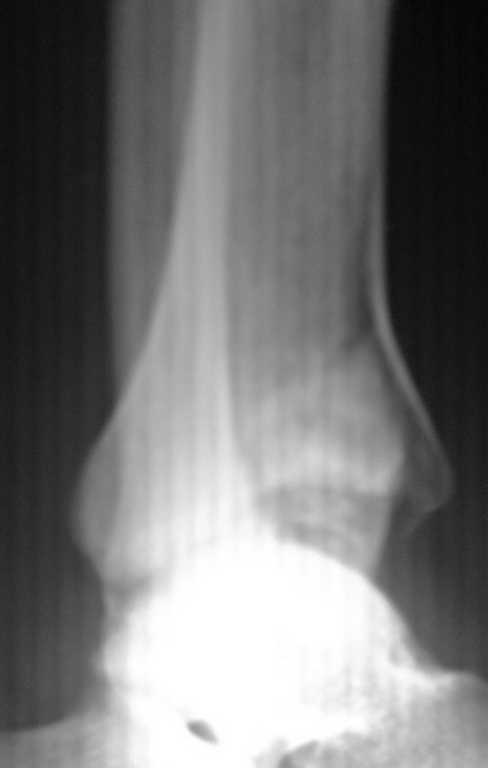

Re: Перелом дистального метаэпифиза ББ кости

Приветствую ! Что то вторая проекция не прошла :((

Пересылаю

Здравствуйте. Я думаю что нужно использовать передний доступ. Заодно нужно мыть область гребень подвздошной оксти. Вполне может потребоваться аутопластика - все таки вполне серьезная импрессия.

Фиксатор - LCP Pilon Plate 2.7/3.5

Он позволит фиксировать при необходимости и сам трансплантат, и получить мостовидную фиксацию в области импрессии. Неблокируемые пластины в случае восстановления суставной поверхности с импрессионым дефектом будут иметь ограниченную дистальную опору, что неблагоприятно скажется на фиксации.